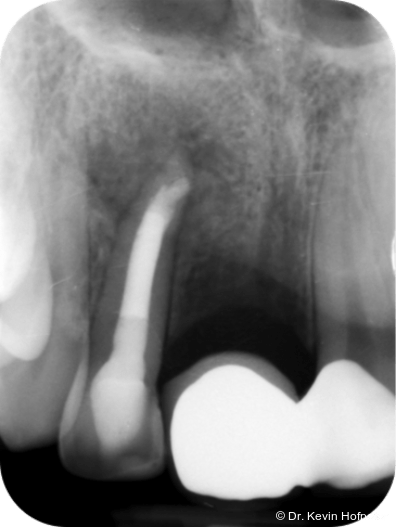

Klinisch zeigten sich die Zähne 12 und 13 karies- und füllungsfrei. Zahn 12 reagierte nicht auf Sensibilitätstests und war leicht perkussionsempfindlich. Zahn 13 reagierte unauffällig. Radiologisch zeigte sich eine ausgedehnte apikale Aufhellung am Zahn 12 sowie eine Hartgewebsformation im apikalen Kanallumen (Abb. 1–2d).

Geplant wurde eine Wurzelkanalbehandlung an Zahn 12. Die zunächst vorgesehene Zystektomie mit Wurzelspitzenresektion wurde zurückgestellt, um die Heilungstendenz nach orthograder Therapie zu beurteilen und einen chirurgischen Eingriff möglichst zu vermeiden.